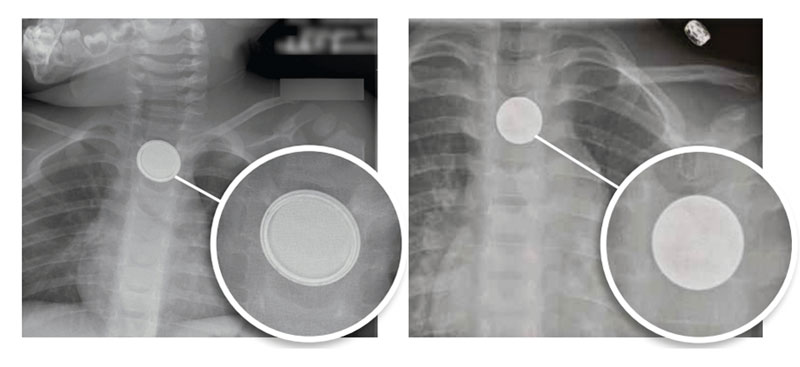

Brett skadepanorama hos barn som svalt ett batteri